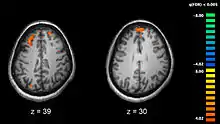

Recent research using neuro-imaging technology including PET and fMRI scanning has shown that there is an extensive amount of distributed brain activation during the process of episodic encoding and retrieval. Among the various regions, the two most active areas during the constructive processes are the medial temporal lobe (including the hippocampus) and the prefrontal cortex.[15] The Medial Temporal lobe is especially vital for encoding novel events in episodic networks, with the Hippocampus acting as one of the central locations that acts to both combine and later separate the various features of an event.[16][17] Most popular research holds that the Hippocampus becomes less important in long term memory functioning after more extensive consolidation of the distinct features present at the time of episode encoding has occurred. In this way long term episodic functioning moves away from the CA3 region of the Hippocampal formation into the neocortex, effectively freeing up the CA3 area for more initial processing.[17] Studies have also consistently linked the activity of the Prefrontal Cortex, especially that which occurs in the right hemisphere, to the process of retrieval.[18] The Prefrontal cortex appears to be utilized for executive functioning primarily for directing the focus of attention during retrieval processing, as well as for setting the appropriate criterion required to find the desired target memory.[15]